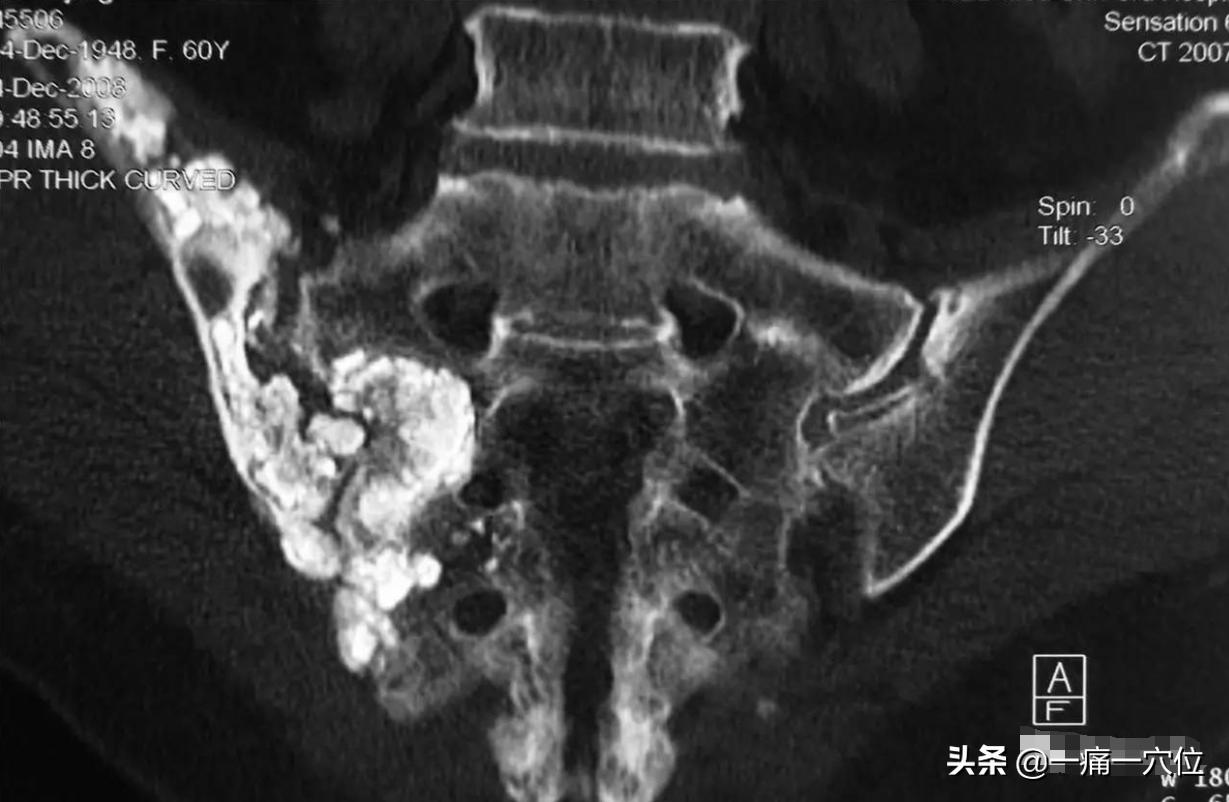

尾骶疼痛的特点是长时间取坐位,或从坐位起立时,或挤压尾骨尖端时疼痛加重,偶有腰骶下部及沿坐骨神经分布区产生疼痛。严重者大便时疼痛加剧,用力排便时尤为明显,卧床休息后疼痛缓解。

由于有多数重要肌肉及韧带附着,如臀大肌、肛门括约肌,肛提肌、尾骨肌,骶尾韧带,直肠的一部分臀大肌附着在尾骶关节上,有时臀部、会阴部也会感到不舒服。坐位时用枕头或者海绵当从垫,可减轻尾骶部位的受压而减轻疼痛。

女性尾骶疼痛要注意排除妇科疾患,因为慢性盆腔炎或者宫颈糜烂较重时可沿子宫骶韧带、主带扩散而导致盆腔结缔组织炎,引起腰骶部及下腹部疼痛,并伴有下坠感。请大家务必将症状清楚。因为这是图文没有办法给大家示范,如有不明白着大家可以留言,个人想办法帮助更多的人。做到中医应尽的责任,让患者早日康复。希望本文章可以帮助到更多的人,让更多的人喜欢中医,爱上中医,用自己可以用穴位来调理自己的身体,也欢迎大家在下面留言,我们一起学习、一起进步、一起交流。再见